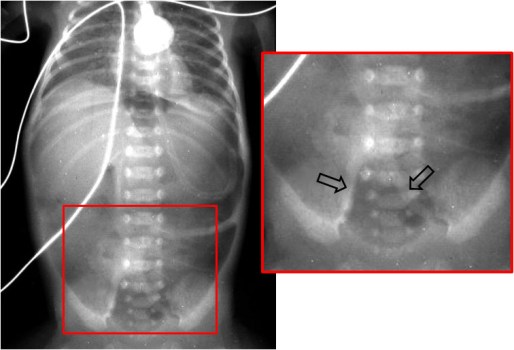

SIGNO DEL BALÓN DE RUGBY

Signo de neumoperitoneo masivo visible en la radiografía simple de abdomen. La forma que adopta el aire en la cavidad peritoneal recuerda la morfología de un balón de rugby. Este signo es más fácilmente visible en niños. Este caso corresponde a un neumoperitoneo masivo secundario a enterocolitis necrotizante en un neonato. En la zona ampliada podemos ver aerobilia.